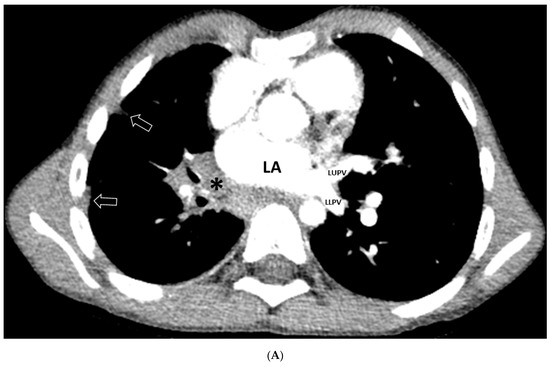

3.2.1. Lung and Airway Abnormalities

3.2.3. Mediastinal Abnormalities